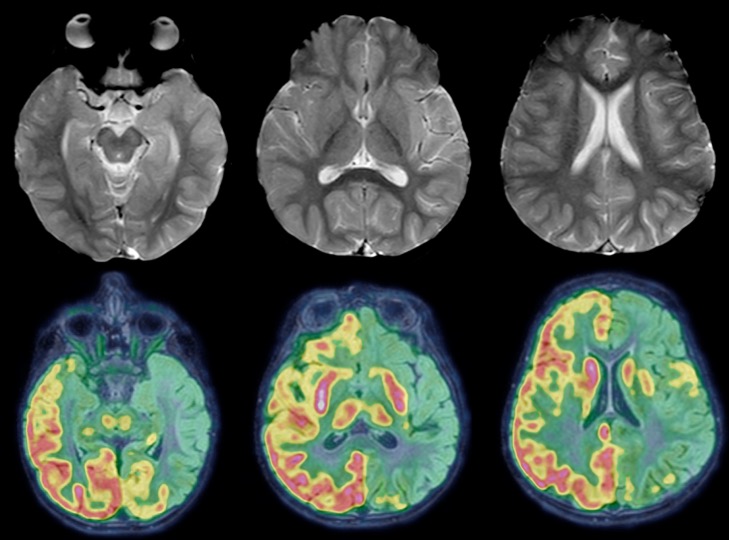

l’hémisphérotomie est une intervention majeure indiquée dans de rares cas d’épilepsie résistant à tous traitements, lorsque les crises viennent d’un seul côté du cerveau ; dans ces cas, l’hémisphère malade n’a plus de fonctions utiles aux patient, il n’a plus qu’un rôle délétère en diffusant l’épilepsie à l’hémisphère sain ; il empoisonne littéralement l’hémisphère sain par libération de toxines. lorsque l’épilepsie est contrôlée par l’hémisphérotomie, l’enfant peut se développer au plan de son éveil mais il garde des séquelles majeures au plan moteur et visuel.

il s’agit d’une intervention majeure qui consiste à déconnecter complètement le cortex de l’hémisphère malade en laissant en place le thalamus ; celui-ci permet de reprendre en charge certaines fonctions, du fait de la neuroplasticité de l’enfant.

le principe est de déconnecter toutes les voies de conduction de la substance blanche en laissant le thalamus seul en place.